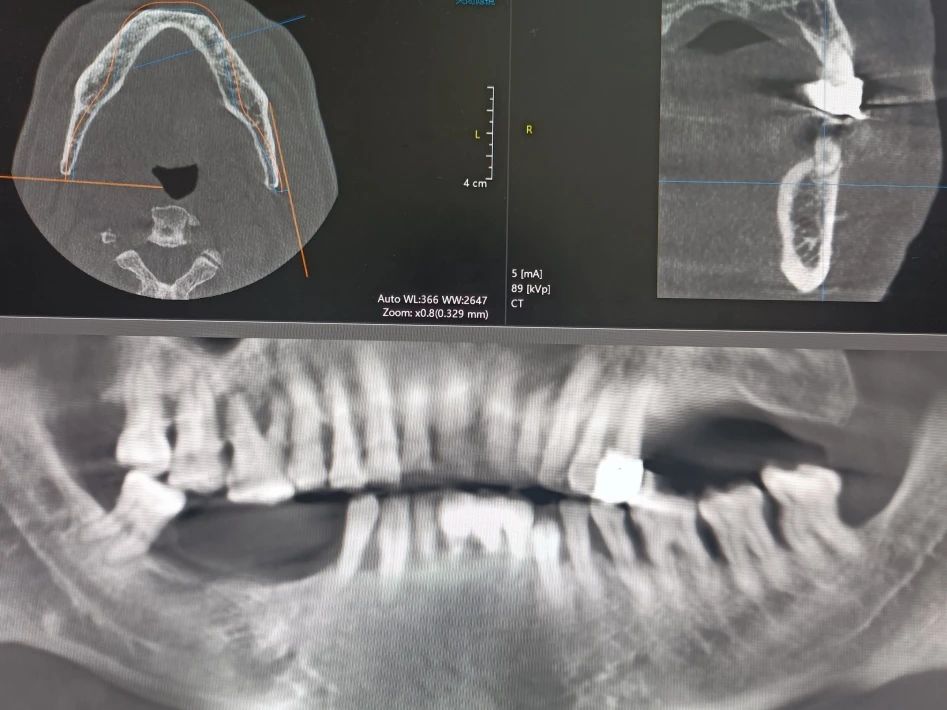

-下颌即刻种植+即刻修复前-

-下颌即刻种植+即刻修复中-

-下颌即刻种植+即刻修复后-

-下颌即刻种植+即刻修复前-

-下颌即刻种植+即刻修复中-

-下颌即刻种植+即刻修复后-